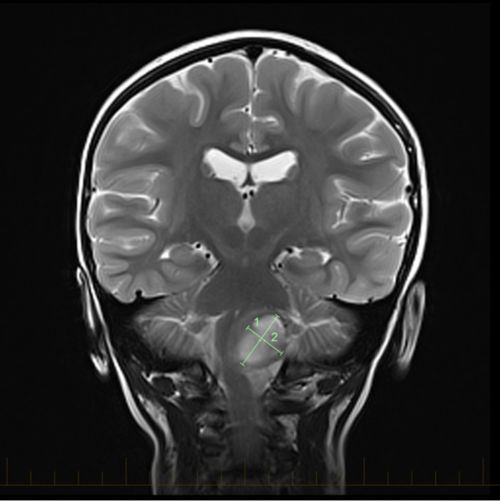

Plano Sagital Rm Craneal Visualizacion De Atrofia Cerebelosa Moderada Download Scientific Diagram

Spinocerebellar Ataxia 36 Sca36 Costa Da Morte Ataxia Neurologia English Edition